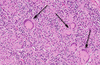

You perform an excisional biopsy on a radiolucent lesion of the mandibular premolar region. A representative section from the specimen is shown below. What is the best diagnosis? a. Lateral periodontal cyst b. Odontogenic keratocyst c. Glandular odontogenic cyst d. Ameloblastoma e. Calcifying odontogenic cyst

a. Lateral periodontal cyst The image shows the architecture of a cyst, including a lumen, epithelial lining, and fibrous connective tissue wall, therefore choice D is incorrect. The exact type of cyst is determined by the features of the epithelial lining. The lining shown is thin (1-3 cell layers thick) with focal thickenings. The diagnosis is therefore A, lateral periodontal cyst. An odontogenic keratocyst (B) will have a lining that is ~6-8 cell layers thick, has a palisaded basal cell layer, and is covered by a corrugated surface of parakeratin. A glandular odontogenic cyst (C) will have a lining of variable thickness and other features including mucous cells, apocrine snouting, microcysts, and cilia. A calcifying odontogenic cyst (E) will have aberrant keratinocyte formation known as “ghost cells.”